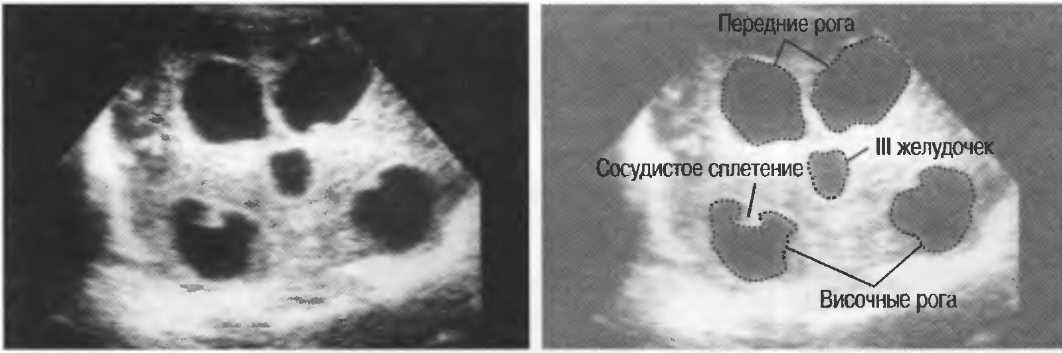

3. Ультразвуковые исследования в педиатрии. Для детей необходим датчик с частотой 5 МГц с глубиной фокусировки на 5-7 см. При исследовании мозга новорожденного используется секторный датчик с частотой 7,5 МГц с глубиной фокусировки на 4-5 см (этот датчик также используется для исследования яичек и структур шеи у взрослых).